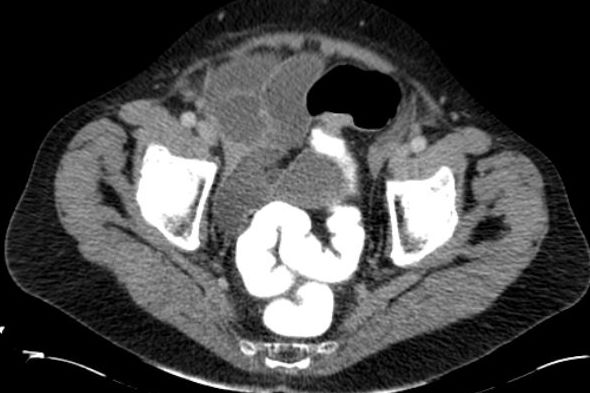

| Ileus | 78-jährige Frau in der Notaufnahme wegen Ileus. Tumor am deszendo-sigmoidalen Übergang. Hemokolektomie: Ulzeriertes Adenokarzinom pT3b pN1a (1/12)Mo L1 Vo. | ||

![]() |

![]() | |

| Ileus | Das CT zeigt einen stenosierenden Sigmatumor mit ausgeprägtem Ileus. |